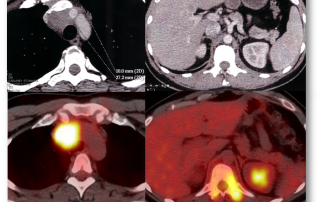

La TEP au 18-FDG